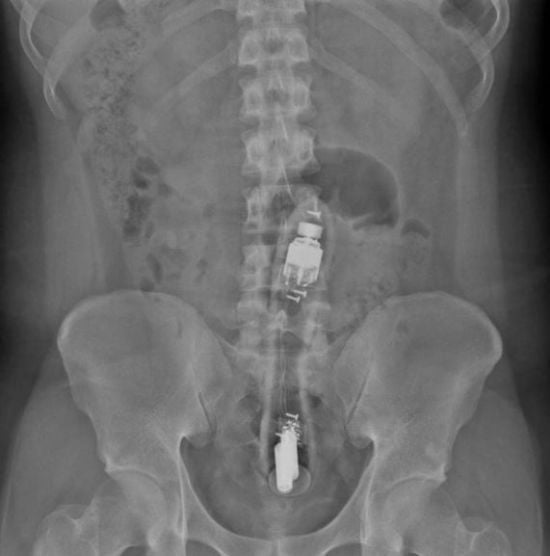

Нажаханий чоловік жалівся на біль у сідницях: його знудило після знахідки всередині (фото)Від mik / 15.03.2025 У пацієнта всередині виявили 20-сантиметровий увімкнений вібратор.